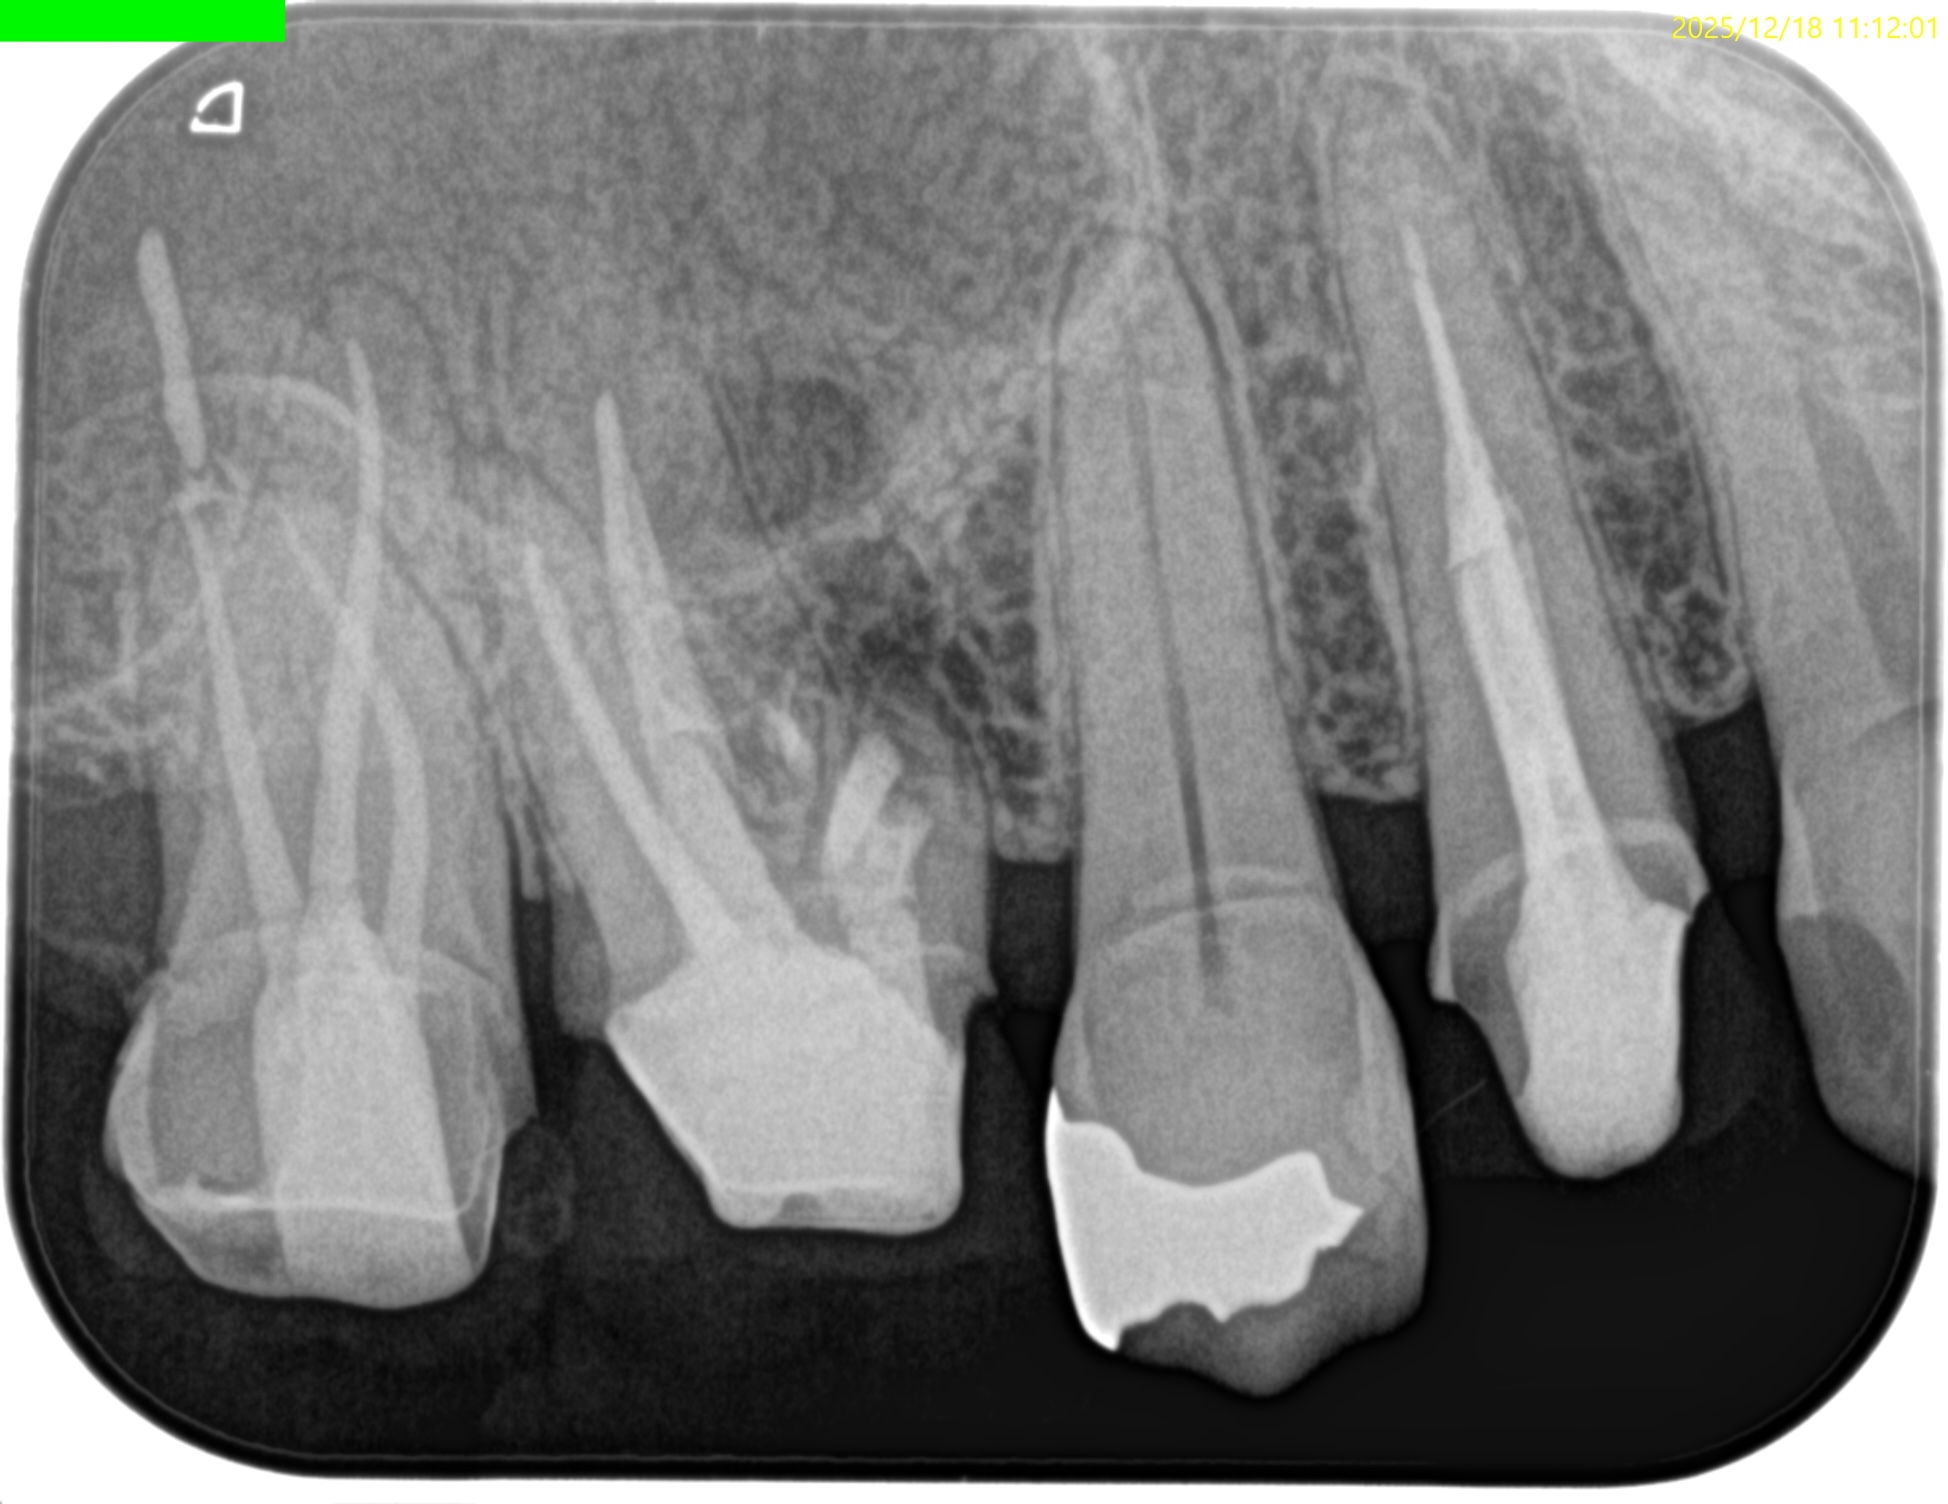

紹介患者さんの治療で、#3 MB Apicoectomyを行ったのだが

MBをRoot resectionした。

ここまでは容易なのだが、この後に逆根管形成・逆根管充填を行うが、

明後日の方向に逆根管形成・逆根管充填してしまう

この状態ではMB2の封鎖がままならない。

つまり、やり直しが必要だ。

その際は、この穿孔部を消去したいので

さらに切断部位から4mm, 頬舌的幅径が6.7mm必要だが再切断し逆根管形成・充填を試みることにした。